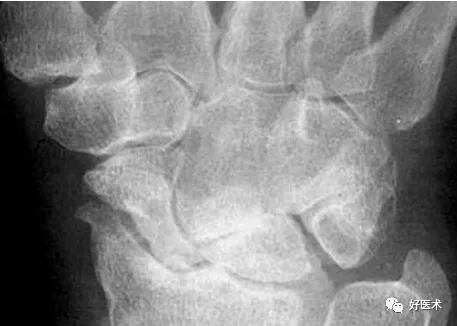

上圖顯示月骨和頭狀骨、鉤骨、三角骨異常重疊,而舟骨與其也不平行,橈月關節間隙異常增寬,其它腕骨間隙平行而勻稱。此為單純月骨脫位。

月骨脫位和月骨周圍脫位

月骨脫位

月骨周圍脫位

最常見的腕骨脫位。區分要點:哪塊腕骨正對橈骨?若頭狀骨正對橈骨而月骨傾斜則為前者;若月骨仍正對橈骨而頭狀骨向背側移位則為後者(圖)。

正位片示舟月關節間隙消失,腕骨弧線不連續;側位片示橈骨遠端的關節面不與月骨平行,月骨倒立,就像立著的一個香蕉或一片橘子,並且向前突出移位。其他腕骨位置正常。

正位片示M形腕掌線和腕骨弧線不連續,腕骨角140°(>130°);側位片示月骨和橈骨相對位置正常,月骨遠端的凹形關節面空虛,其他腕骨一起向後移位,形似懸掛在月骨後上方的花托。月周脫位常伴有舟骨骨折,本例亦顯示舟骨橫行骨折。